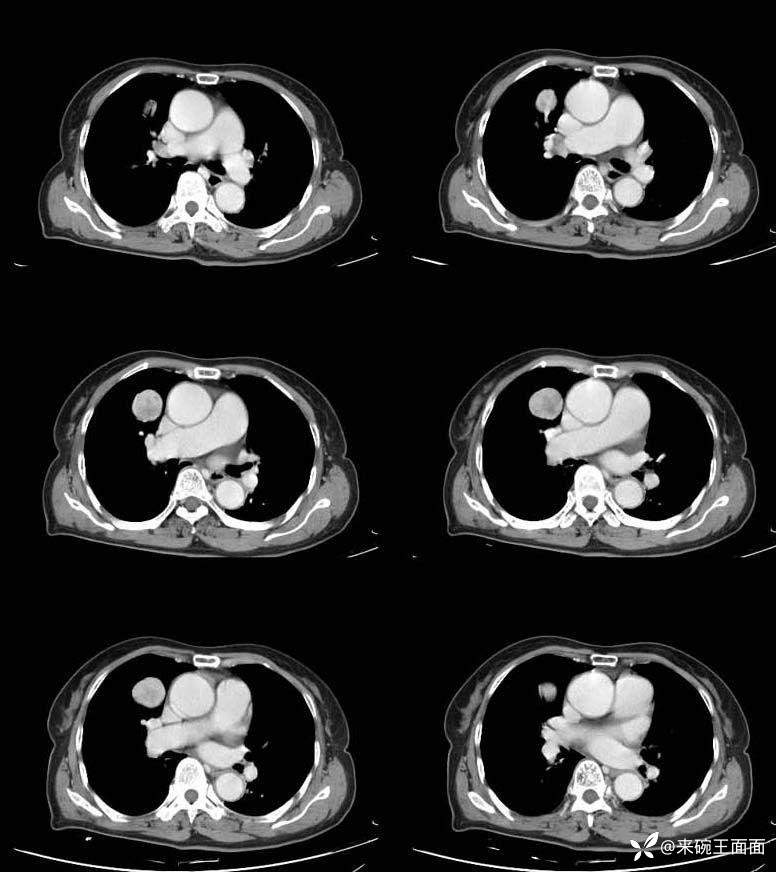

详情:右肺门类圆形肿块,边缘光整,增强扫描肺门侧可见一血管与肿块相连,且该病灶边界清晰,其密度均匀。对周围结构无明显影响。